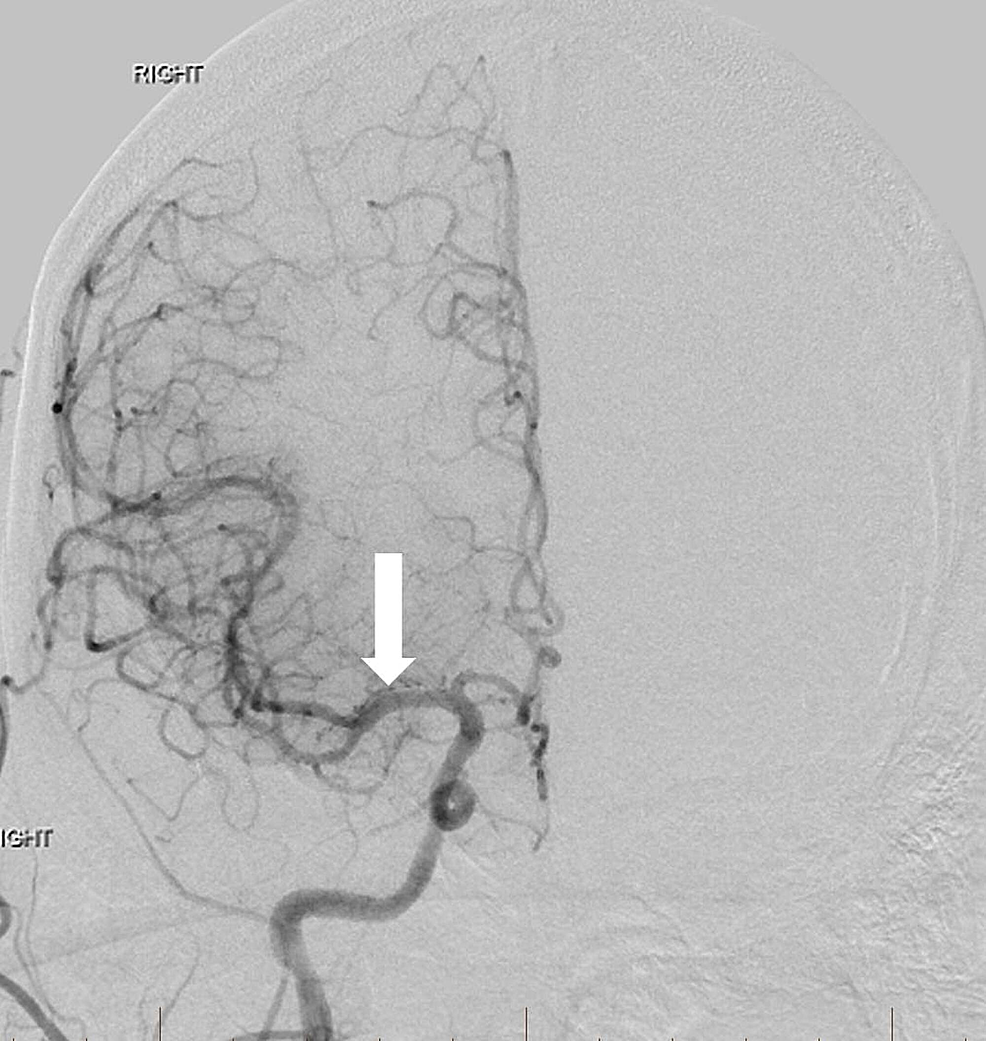

A 63-year-old man with a history of hypertension, hyperlipidemia, peripheral artery disease, smoking, and Stage IV lung cancer presented with left-sided weakness and dysarthria when he visited our institution for a chemotherapy port placement. His National Institutes of Health Stroke Scale (NIHSS) score was six and he was not a candidate for intravenous (IV) thrombolytics. Computed tomography angiography (CTA) revealed occlusion of the extracranial right internal carotid artery (ICA) and right middle cerebral artery (MCA) but no hemorrhage or large areas of acute ischemic change. Biplane digital subtraction angiography (DSA) revealed tapering to occlusion of the proximal right cervical ICA at the level of the carotid artery bulb (Figure 1).

Angioplasty was performed at the level of the severe proximal ICA occlusion using a 4 mm x 20 mm noncompliant balloon. Subsequent angiography demonstrated the progression of contrast into the distal cervical and intracranial segments of the ICA with a persistent severe and irregular stenosis. A decision was then made to stent using distal embolic protection. A 4-mm diameter distal protection device was advanced and deployed in standard fashion within the distal cervical ICA at the level of C1-C2. An eptifibatide infusion was started, and an 8 mm to 6 mm tapered self-expanding carotid stent measuring 40 mm in length was positioned across the lesion and deployed in the standard fashion without angiographic complications. Post-stenting angiography revealed a 90% improvement in the caliber of the occluded vessel without delay in transit time throughout all cervical and intracranial right ICA segments (Figure 2).